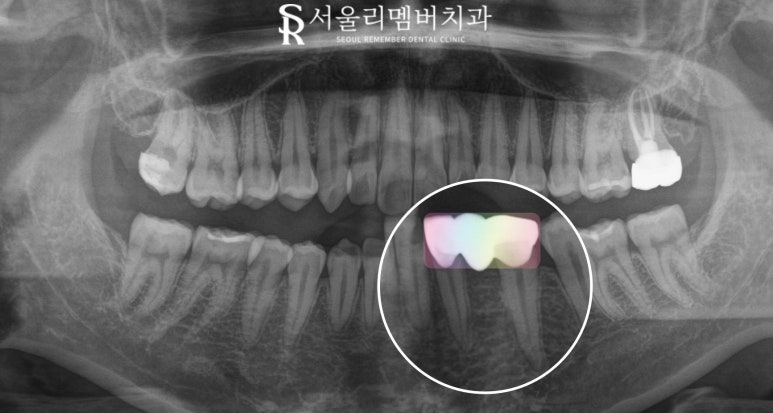

이 케이스는 이미 동요도가 크게 존재하고

영구치의 치배가 보이지 않는 상황이었으므로

이 자리에 임플란트를 심기로 했습니다.

그러나 크라운을 올리기에는

공간이 다소 좁아

보철의 크기가

작게 느껴질 수 있다는 것을 고려하여

환자와 충분한 대화 끝에

측절치부터 첫 번째 작은 어금니까지

브릿지를 수복하기로 계획했습니다.

유치는 조심스럽게 뽑았으며

양옆의 치아를 지대치로 하여

브릿지를 제작하였습니다.

지대치의 치주 상태,

치근 길이, 치수 감염 여부와 같은

여러 조건을 평가해 보았을 때

브릿지로 수복했을 때

충분히 오래 사용하실 수 있을 것이라 판단되어

보철을 씌우게 되었습니다.

물론 이때 서울대입구역 치과 에서

얼마나 최소한의 양만큼 치관을 다듬어서

보철을 씌우느냐가 중요한 만큼

프랩 과정을 섬세하게 진행하였습니다.

모든 보철 수복을 마친 모습인데요,